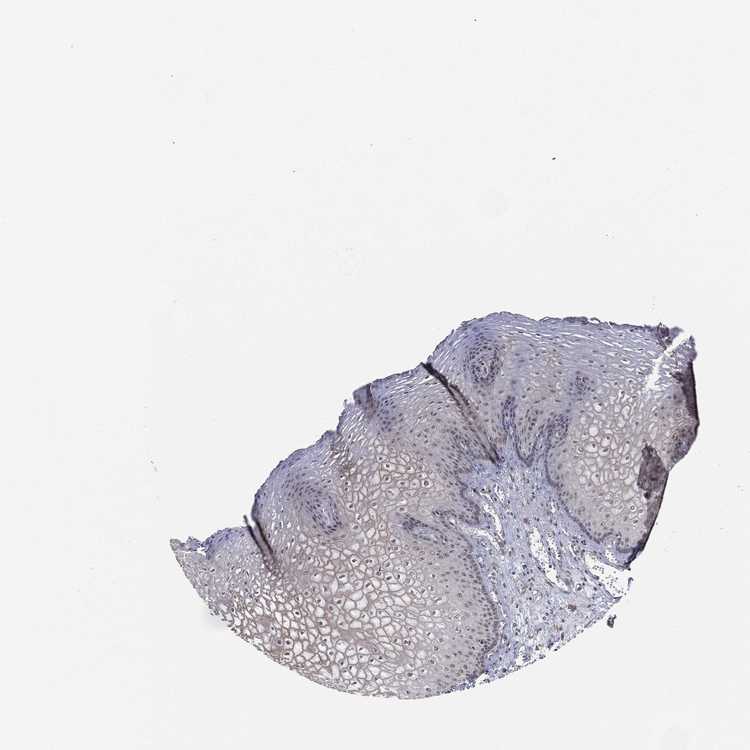

ESOPHAGUS - Antibody stainingi

Antibody staining in the annotated cell types in the current human tissue is reported as not detected, low, medium, or high, based on conventional immunohistochemistry profiling in selected tissues. This score is based on the combination of the staining intensity and fraction of stained cells.

Each image is clickable and will lead to virtual microscopy that enables deeper exploration of all samples and also displays staining intensity scores, fraction scores and subcellular localization as well as patient and tissue information for each sample.

Antibody HPA040070Antibody HPA048183

Squamous epithelial cells HighHigh